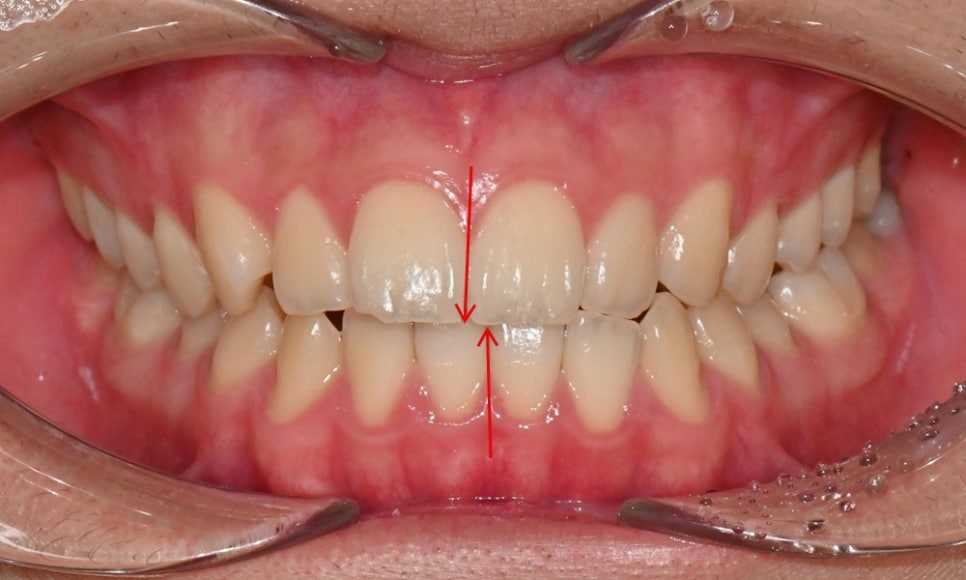

외관상으로는 아랫입술이 돌출되어 보이고 아래 치아가 좌측으로 치우치면서 치아 중심선(midline)이 맞지 않는 상태였습니다. 또한 환자는 어릴 적 넘어지면서 앞니가 깨졌던 외상 병력이 있었고, 그 영향으로 앞니 뿌리가 부분적으로 흡수된 상태였습니다.

2024.12. 초진 구내사진 - 연세정원치과

정밀 검진 결과, 하악 치열이 좌측으로 틀어져 있었고 그로 인해 위아래 치아 중심선이 일치하지 않았습니다. 아래 치열이 전체적으로 전방 위치하여 아래 입술 돌출이 더 도드라져 보이는 상태였습니다. 그리고 상악궁이 하악궁보다 좁아서 앞니 부위 일부 반대로 물리는 치아 교합도 관찰되었습니다. 특히 외상 치아의 경우, 교정력 적용시 추가적인 염증성 치근 흡수 위험이 존재하기 때문에, 치료 중 지속적인 관찰이 필수적인 상황이었습니다.